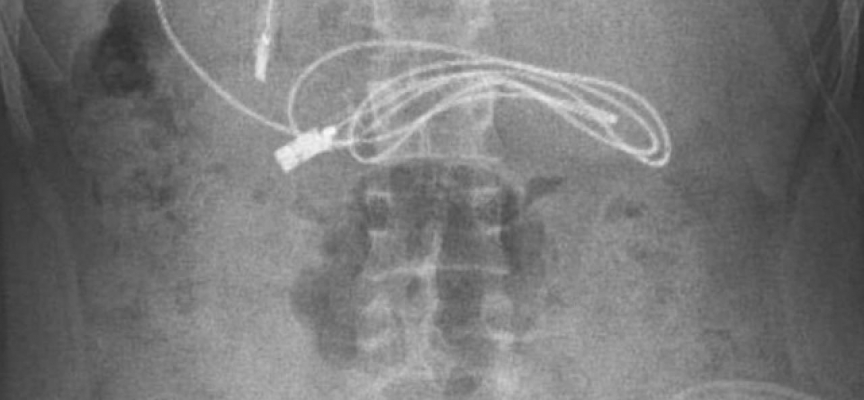

Diyarbakır'da kusma ve bulantı şikayetiyle hastaneye giden 15 yaşındaki erkek çocuğunun çekilen röntgeninde, midesinde şarj kablosu ve toka olduğu tespit edildi.

Ameliyatı gerçekleştiren Prof. Dr. Yaşar Doğan, kablonun bir ucunun ince bağırsağa geçmesi nedeniyle zorlandıklarını ifade ederek, “Hastanın kusma ve karın ağrısı şikayetleri olması üzerine sağlık kuruluşuna başvurulmuş. Orada yapılan incelemelerde hastanın midesinde kablo tespit edilmesi üzerine bize danışıldı. 112 aracılığıyla hastaya gerekli işlemi yapıp yapmayacaklarını bize sordular. Biz de hastayı bize gönderebileceklerini kendilerine ilettik. Hasta bize geldikten sonra ön hazırlık yapıldı ve gerekli olan açlık süresinin ardından hastaya endoskopik işlem yapıldı. Endoskopik işlemle midedeki kablo çıkarıldı. Kabloyu çıkarırken açıkçası zorlandık, çünkü kablonun bir ucu ince bağırsağa geçmişti. İşlem başarılı bir şekilde sonlandırıldıktan sonra hasta sağlıklı bir şekilde evine gönderildi” dedi.